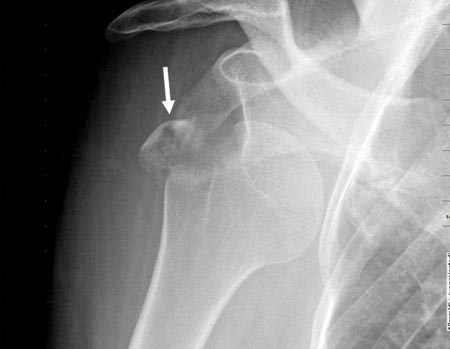

Figura 1A: Fractura con desplazamiento del troquiter mayor a 5 mm./ Figura 1B: Misma fractura en TAC 3D. Conminuta a 3 fragmentos y desplazada. Flechas: fragmentos óseos.

Figura 1C: Espacio subacromial. Reducción artroscópica fractura del troquíter. Se observa línea de fractura./ Figura 1D: Osteosíntesis artroscópica con tornillos canulados de 3.5 mm./ Figura 1E: Reducción y ostesíntesis con 3 tornillos canulados de 3.5 mm. Flecha: pérdida de hueso. Reparación de Bankart y SLAP asociada.